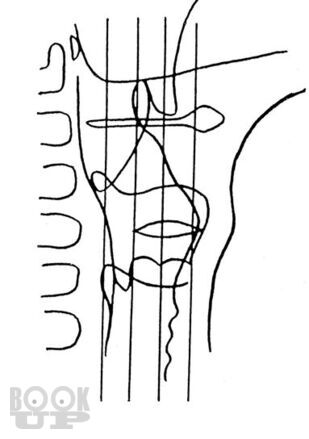

Книга П.В. Власова посвящена традиционным методам рентгенологического исследования пищеварительного тракта. В последние 20 лет периодическая печать заполнена публикациями, посвященными новым, модным и актуальным вопросам применения новейших методов лучевой диагностики, таких как ультрасонография, компьютерная и магнитнорезонансная томография. Между тем как подавляющее большинство рентгенологов в своей практической работе используют традиционные методы рентгенологического исследования, являющиеся базовыми, первичными в клинической диагностике различных заболеваний.